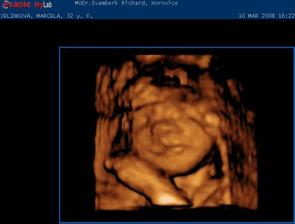

Jako v pohádce. 1.9.2007 jsme měli svatbu. 18.9.2007 jsme odjeli do Egypta na svatební cestu. Ze které jsme přijeli ve třech. Opravdu se nám to povedlo. 7.10.2007 jsem nedostala MS 10.10.2007 HURÁ !!!! Těhoteský test pozitivní. 12.11.2007 první KO, jsem 9+1 tt. Pan doktor mi dělal UTZ, dal mi první fotku mimíška. Těhotenství potvrzeno na 100 %,dostala jsem Těhotenskou průkazku. 29.11.2007 11+6 tt Byla jsem na odběru krve. Mám nízký tlak. 10.12.2007 13+3 tt KO viděla jsme opět mimíško na UTZ, má se čile k světu. Krev je vpořádku. 13.12.2007 potvrzení od obvodní lékařky a měření EKG. 3.1.2008 16+4 tt KO odběr krve na Triple test. UTZ mimíšku pěkně bije srdíško. Mám stále nízký tlak. Berou mě křeče do lýtek a pálí žáha. Pan doktor mi napsal MagneB6. 19.1.2008 18+6 tt už se pomalu do ničeho nevejdu. První nákup těhu kalhot a těhu blůza. 22.1.2008 19+2 tt dnes ráno jsme cítila jak mě mimíško několikrát koplo. A dopoledne v práci jsem cítila takové šimrání v bříšku. 28.1.2008 dneska jsem koupila mimíškovi první bodíčka. 31.1.2008 20+4 tt KO Trile test nagativní. Pan doktor mi dělal UTZ a pravděpodobně to bude KLUK. Poznala jsme to i já. Mimíško už váží 400g. Manžel měl radost. 4.2.2008 21+1 tt první těhotenské plavání. Bylo to moc pěkné a myslím, že i mimíšku v bříšku se to líbilo. 9.2.2008 – 16.2.2008 mám dovču. Jeli jsme na hory, ale já jsme raději nelyžovala, abych neublížila mimíšku. Vynahradím si to až příští rok. Hodně jsem odpočívala a chodila na procházky. 18.2.2008 kontrola u zubaře. Vše v pořádku. 19.2.2008 v práci mi bneska hodně tvrdlo a bolelo břicho. Tak uvidím jak mi bude zítra. 20.2.2008 23+3 tt opět mě tvrdlo a bolelo břicho až do zad. A docela intenzivně. Popráci jsem šla rovnou k doktoru. Vyšetřil mě a říkal, že to není moc dobré. Raději mi napsal neschopenku. 21.2.2008 bolí mě v kříži, především při chůzi. Jen doufám, že to nebude až do konce těhulkování. 27.2.2008 24+3 tt dneska jsem šla k obvodní doktorce s tou bolavou kyčlí. Stále mě dost bolí. Poslala mě na těhotenské cvičení, kde mi ukážou nějaké uvolňovací cviky a mám odpočívat. Snad to přejde. 5.3.2008 25+3 tt těhotenaké cvičení v nemocnici. Sestřička mi ukázala nějaké cviky na uvolnění kyčle a masáž. 10.3.2008 26+1 tt dneska jsme byli s manželem na 4 D UTZ. Bylo to moc hezké, mimíško se nám hezky ukázalo. Dokonce jsme viděli, že je to opravdu kluk. Pan doktor nám udělal nějaké fotky a nahrál mimíško na DVD. Je to opravdu moc krásný a jedinečný zážitek. 11.3.2008 26+2 tt dnes jsem byla v nemocnici na testu na cukrovku. 13.3.2008 začala jsme chodit do Solné jeskyně. Moc pěkně se tam relaxuje. Rozhodně to všem doporučuji. 19.3.2008 Dnes velký nákub oblečků na mimíško. 20.3.2008 27+4 tt KO test na cukr mám v normě. Tlak stále nízký a žáha mě pořád pálí. Bolest kyčle už ustoupila. Parvděpodobně mimíško změnilo polohu a netlačí už na nic. 29.3.2008 Byli jsme se podívat na kočárek. Nakonec se nám nejvíce líbí kočárek JANE SLALOM PRO, barva hnědooranžová. 10.4.2008 začala jsme chodit na těhu cvičení na Gymbalonech. 16.4.2008 první hodina předporodní přípravy. 17.4.2008 31+4 tt KO UTZ mimíško podle měření už váží 2100g, doufám, že to nebude žádný obřík. Jinak se má k světu a vše je v pořádku. Byla mi odebrána krev. 25.4.2008 32+5 tt pěkně mě bolí v krku. Návštěva obvodní lékařky. Udělala mi výtěr a uvidí podle výsledků. 28.4.2008 výtěr je vpořádku, ještě mě pro jistotu poslala na krční. Prý v těhotenství bývají zduřelé krční mandle. Tak by to mělo přejít samo. Mám brát pouze těhu vitamíny. Dneska jsme si přivezli kočárek. Nechali jsme ho u rodičů, pro jistotu, pověra je pověra, ale kdo ví. 4.5.2008 34 tt nástup na mateřskou dovolenou. Začínám s masáží hráze. 5.5.2008 34+1 tt KO UTZ mimíško už tam nemá moc místa, váží už 2500g, Mám nízké hodnoty železa v krvi. Tak jsem dostala vitamín železo. Magnesium už nemám brát. Dneska jsme byli s manželem v nemocnici, kde budu rodit, na předporodní besedě. Řekli nám, co nás čeká při porodu, a ukázali porodní pokoj. 8.5.2008 doma generální úklid a příprava na mimíško. Oblečky na mimíško mi pere a žehlí mamka, je moc hodná a hodně mi s tím pomáhá. Jsem moc ráda a tato práce mi odpadla a já si domů odvezu už vše hotové. 9.5.2008 34+5 tt celou noc jsem nespala, mám rýmu a strašný kašel. Docela se bojím i o mimíško. Tak jsem raději šla k obvodní doktorce. Ta mě poslechla, mám zánět průdušek. Dala mi antibiotika ZINNAT 250mg. Moc nejsem nadšená. Ujišťovala mě, že se můžou v těhotenství, a i v lékárně mi to říkali. Doma jsem si to našla i na Internetu. Tak snad bude vše vpořádku. 12.5.2008 35+1 tt Dneska jsem byla na natočení na EKG, to prý potřebuji k porodu. 13.5.2008 Opět mě začal bolet kyčel, jak mě již jednou bolel. Asi se mimíško nějak jinak uvelebuje a tlačí mi na nějaký nerv. 15.5.2008 35+4 tt KO doktor říkal, že mě ta kyčel pravděpodobně přestane bolet až po po porodu. Tak nejsem moc šťastná, protože je to dost omezující, především při chůzi. Mimíško je vpořádku. Dneska mi poprvé natáčel monitor, tak jsem slyšela tlukot mimíškova srdíčka. 26.5.2008 37+1 tt Dneska mám narozeniny!!! KO pan doktor mi dělal vyšetření a kultivaci z pochvy. Od příštího týdne už budu chodit na KO do nemocnice, kde také budu rodit. Tak už jsme se rozloučili a mám k němu přijít na KO až po šestinedělí. Snažím se, co nejvíce odpočívat. 2.6.2008 38+1 tt KO už v nemocnici. Výsledky kultivace nejsou moc dobré, tak jsem dostala globule na zavádění. S paní doktorkou jsme se domlouvali na průběhu porodu, protože jsem v minulosti měla zlomenou sedací kost. Domluvili jsme se, že porod necháme přírodní cestou a pokuď bude něco špatně, tak přistoupí k císařskému řezu. Doufám, že bude vše bez komplikací. Opět mi natáčeli monitor. 9.6.2008 39+1 tt KO natáčení monitoru. Je moc hezké slyšet jak mimíšku bije srdíčko. Dneska mi dělala vyšetření, vše je vpořáku. Zítra jdu na UTZ. 10.6.2008 39+2 tt dneska jsem byla na UTZ, kde měřili mimíško. Podle měření váží asi 3509g. Nakonec jsme se s paní doktorkou domluvili, že pokud neporodím do 22.6., tak si v pondělí 23.6. v 8 hodin půjdu lehnout do nemocnice, abych moc dlouho nepřenášela a mimíško nebylo moc velké, vzhledem k té zlomené sedací kosti. No nějak mi to těhulkování moc rychle uteklo a už se ten obávaný porod opravdu blíží, což si nějak moc nechci připouštět. Ale můžu říci, že jsem si to moc užila a ještě užívám. Je to asi opravdu ta nejkrásnější doba v mém životě. Vědět, že v sobě máte mimíško, a těšit se na něj. 16.6.2008 40+1 tt tak dneska už jsme byla na natočení monitoru a na poslední KO. Doktorka mi dělala vyšetření a říkala jak miminko je hezky sestouplé. Prý je dobře připraveno k porodu a vše vypadá, že bych mohla porodit dříve než v pondělí. Aby mi nemuseli porod vyvolávat. Já bych raději chtěla porodit normálně bez vyvolání. Doufám, že se to povede. Jinak v pondělí 23.6.2008 nastupuji do nemocnice. No tak musíme doma zkusit osvědčené babské rady, snad se nám to povede. Mimíško se nějak v bříšku zabydlelo a vůbec se mu nechce ven. Držte nám palečky. Děkujeme. 17.6.2008 40+2 tt od 23.00 hod tvrdnutí bříška, že by to již bylo ono???? Ve 23.43 hod začínají kontrakce po 10 minutách. 18.6.2008 40+3 tt ve 2.30 hod odjezd do porodnice. Kontrakce po 4,5 minutách. V 8.29 hodin DAVÍDEK na světě. Váží 3880g a měří 52 cm. Tatínek byl u porodu a byl moc velkou oporou mamince. Moc si toho vážím. Je to velká odměna a stálo to za to. Těď už jsem ne dva, ale tři. Jedna velká rodina. Jsme moc šťastni.